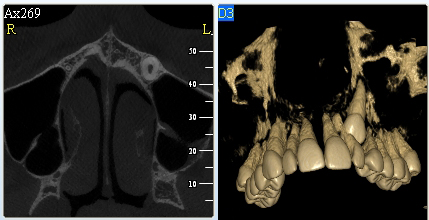

3D DVT - NewTom

Je speciální zubní digitální tříprostorový tomograf (3D), který umožňuje na základě jediného snímkování vytvořit všechny typy RTG zobrazení, které jsou pro lékaře potřebné. Díky používané technologii tzv. „kuželového paprsku“ a speciálním senzorům je výrazně zmenšená dávka záření - o více jak 80% proti klasickému CT vyšetření. To je významné zejména u dětí. Pomocí tohoto přístroje je možné zjisti skutečnou situaci v čelistních kostech pacienta tedy množství kosti - můžeme změřit skutečnou šířku i výšku kosti, i kvalitu kosti (hustotu) v místě uvažované implantace. 3D (tříprostorové) zobrazení umožňuje zvýšit prostorovou představu operatéra ještě před vlastní operací a zároveň pacientovi lépe objasnit a ukázat oblast plánovaného zavedení implantátu.

Pacient „neumí číst“ RTG snímky, ale díky 3D zobrazení vidí „svoji skutečnou čelist“ - např. jak je nízká či úzká, vidí průběh nervu nebo velikost čelistní dutiny, což mu umožní i pochopení nutnosti v některých případech provést pomocné zákroky ještě před vlastním zavedením implantátu (viz. kostní štěp, sinus lift, kostní granulát...).

Vyšetření pomocí tohoto přístroje používáme i ve stomatochirurgii (zlomeniny čelistí, zuby moudrosti, cysty, onemocnění čelistního kloubu), ortodoncii (retinované zuby, nadpočetné zuby), parodontologii atd.